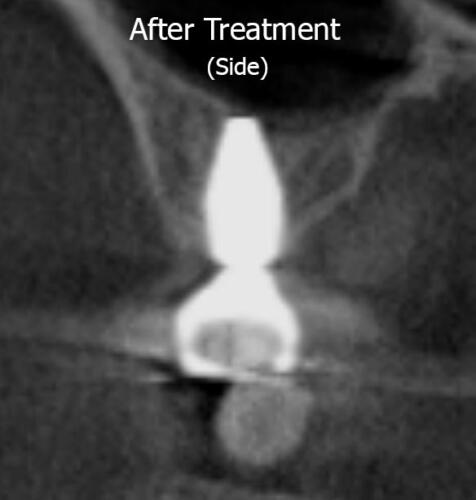

A sinus lift procedure was performed for DM, which lifted the floor of the sinus and resulted in more bone forming (shown by the green dotted line and the transparent overlay of the implant no longer going beyond the green dotted line). This allowed enough bone height in the jaw to facilitate placement of the implant and subsequent crown on top. DM is now able to chew and eat food on high right side, without having a serious sinus infection as a byproduct!